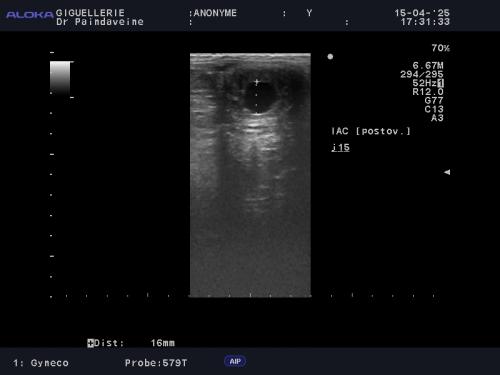

Si l’insémination en semence fraîche ou réfrigérée offre une certaine souplesse, le recours à la semence congelée (IAC) exige une précision chirurgicale. La survie des spermatozoïdes cryoconservés étant réduite, le suivi devient intensif pour garantir un dépôt de semence au plus proche de l'ovulation.